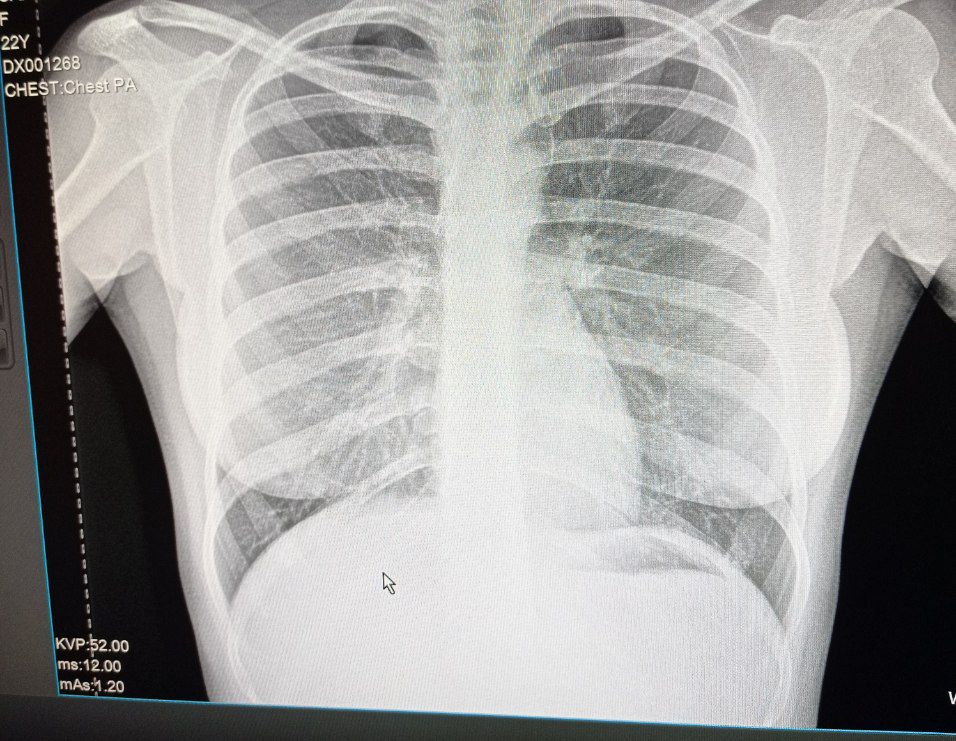

Норма